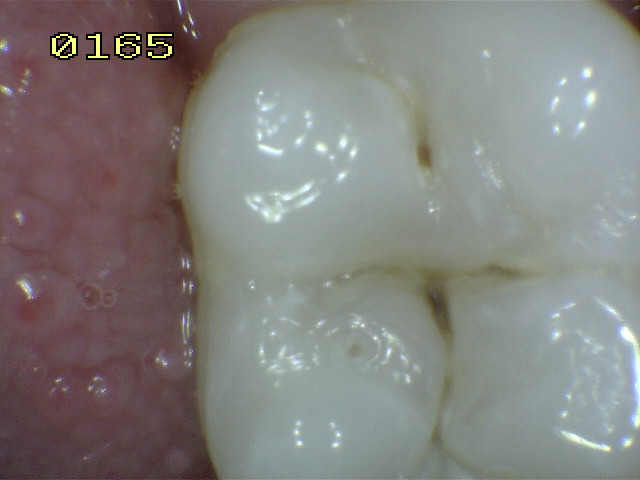

Código 0: No

hay evidencia de caries en esmalte seco.

Las superficies con defectos de desarrollo,

tales como la hipoplasia del esmalte,

fluorosis ( Ddiagnóstico diferencial entre la fluorosis y opacidades del

esmalte), desgaste de los dientes por abrasión y erosión, y las manchas extrínsecas por la

ingesta de mate, té, café o por el habito de fumar y las manchas

intrínsecas se registrará como sano. El examinador también debe

marcar como sano, una superficie con múltiples fisuras pigmentadas si

tal condición se observa en otras fosas y fisuras.